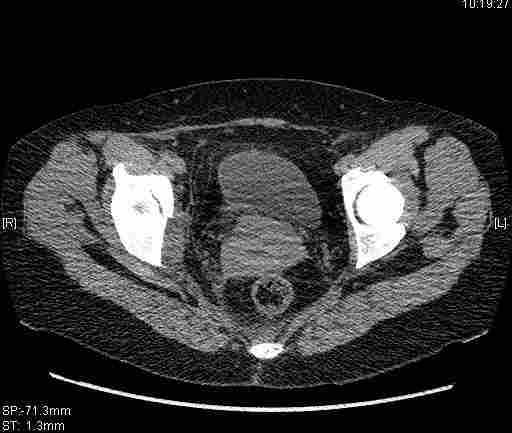

Re: Т-образный перелом вертлужной впадины

Удалось сегодня вывести пациентку в соседнюю больницу, где есть кт. Срезы сделаны только горизонтальные.